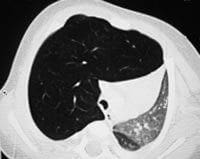

Figuras 2 A, B, C y D. TCAR en inspiración (izquierda) y espiración (derecha). Sobreinsuflación del lóbulo superior derecho

con hipovascularidad y desplazamiento contralateral de las estructuras mediastinales.

En los cortes en espiración las alteraciones descritas son más evidentes.